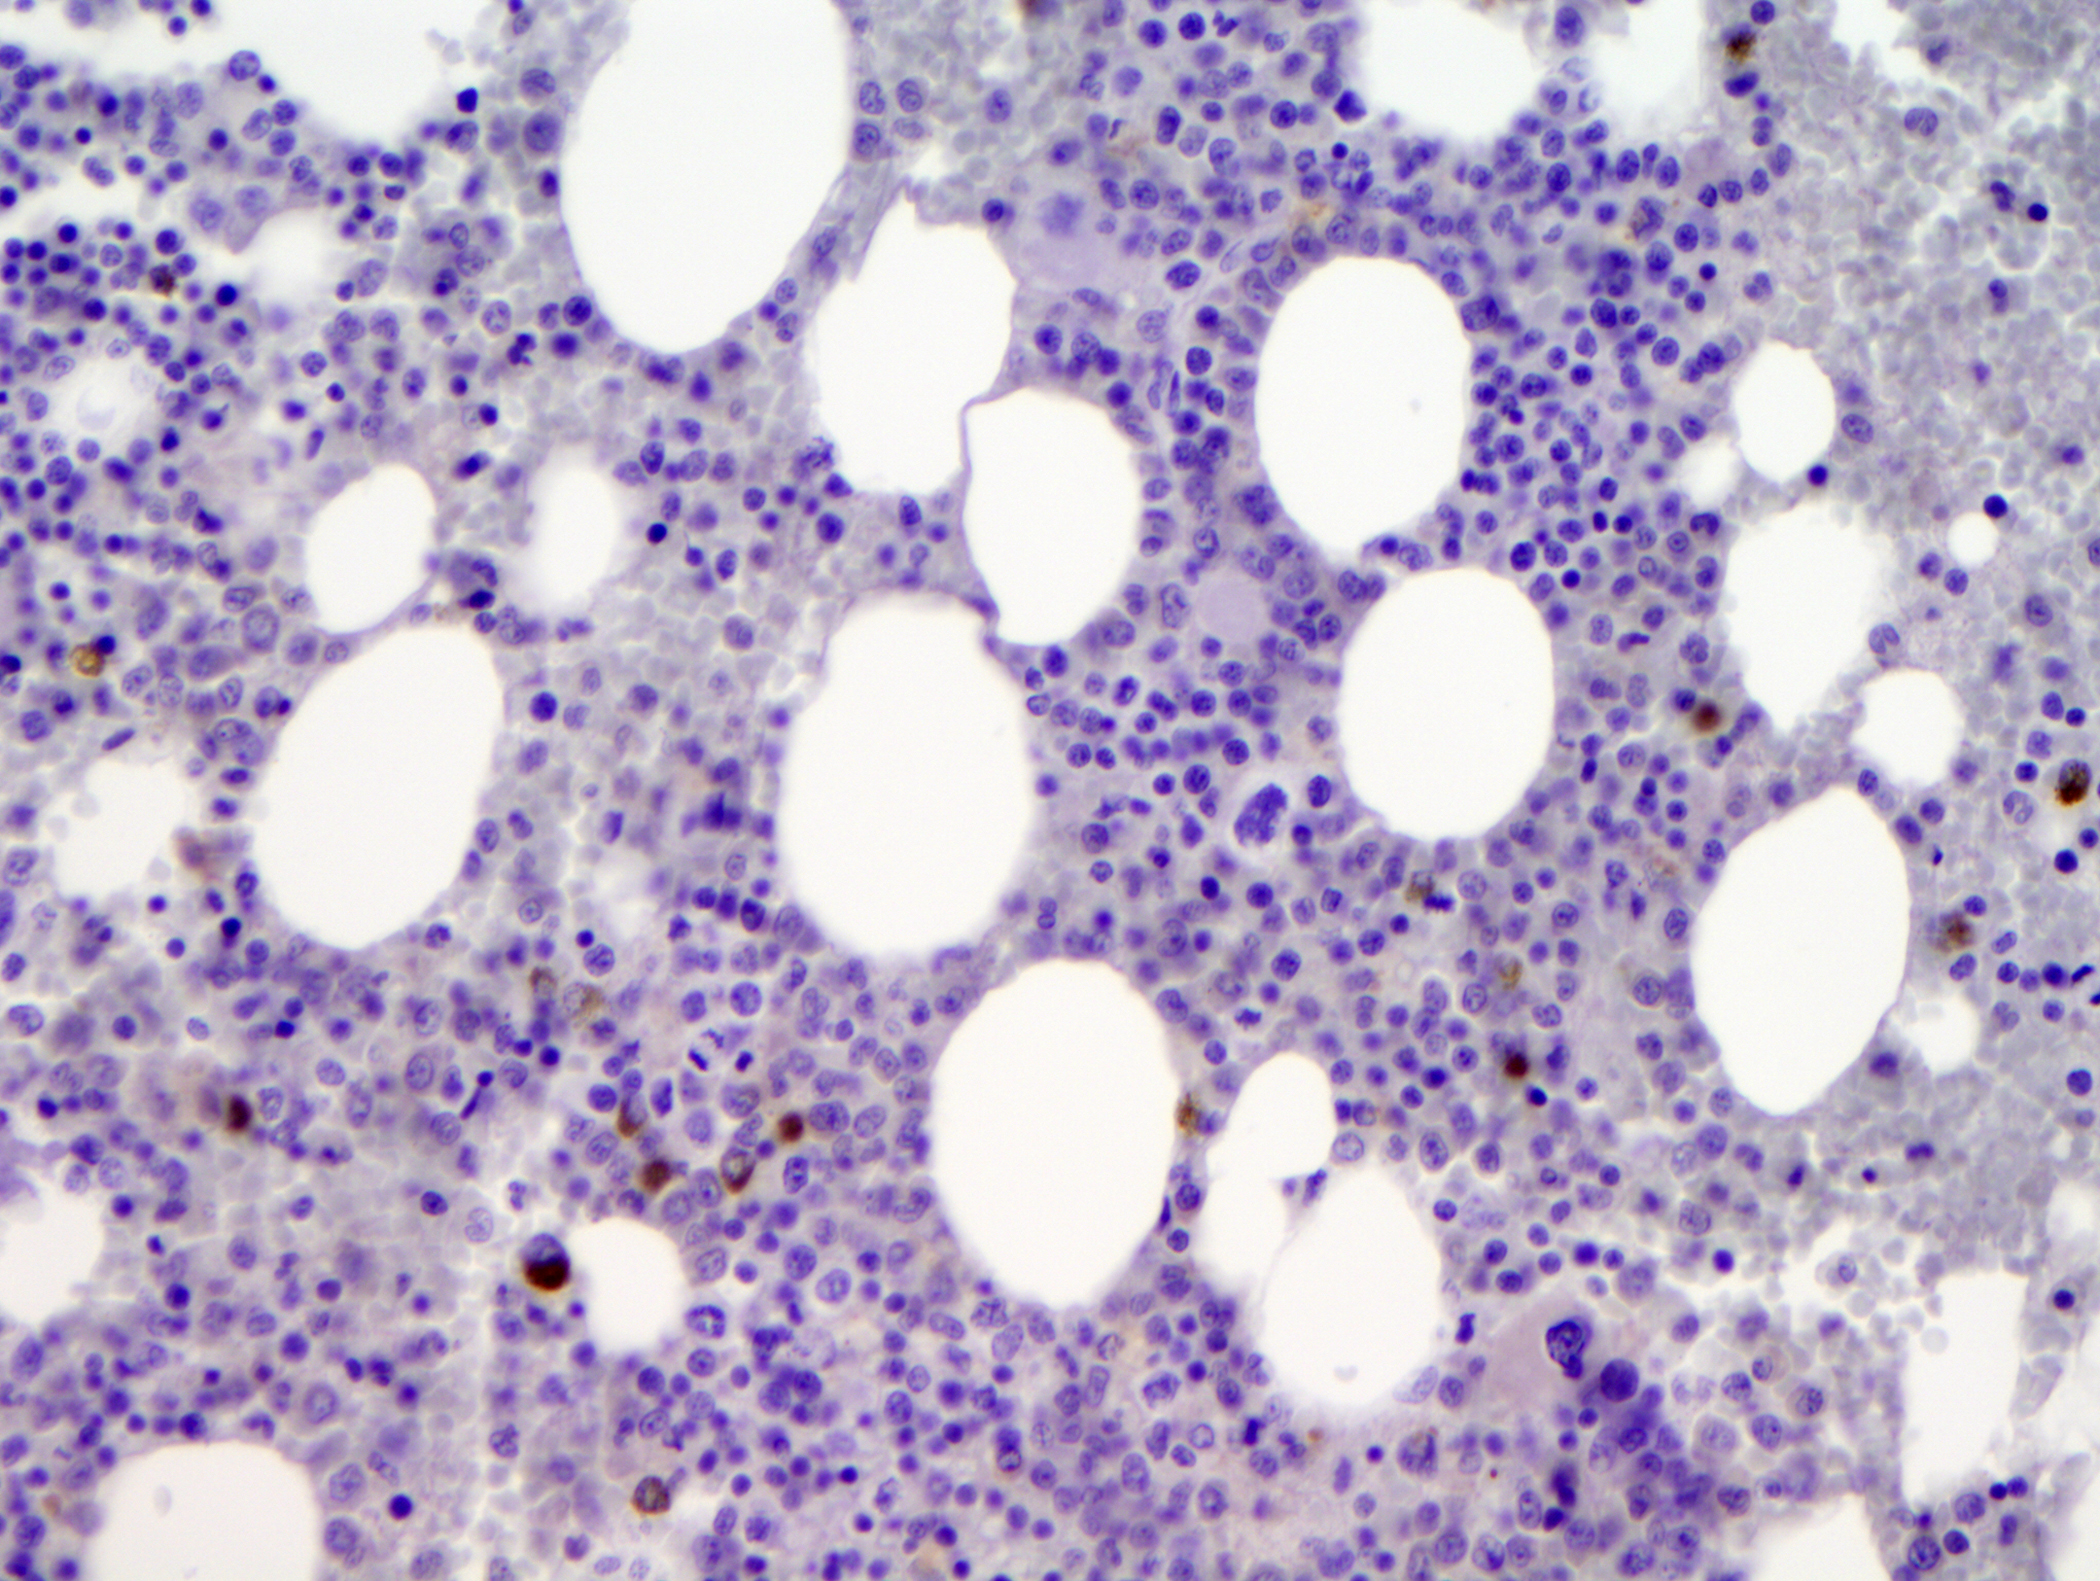

The labyrinth of pyrexia of unknown origin: A case of intravascular B cell lymphoma